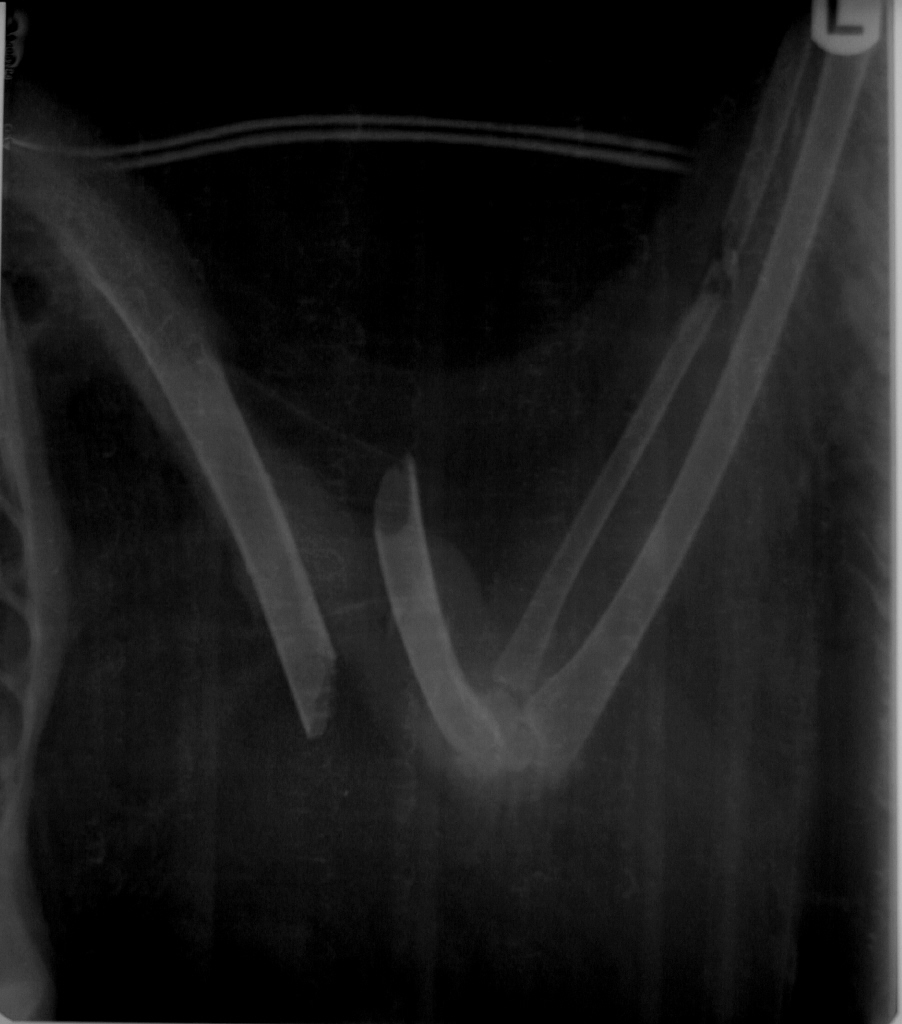

뼈는 이미 밖으로 다 튀어나와 있어 오염이 되었고 사실 절단 혹은 안락사만 지시되는 상황이어서 절단술을 실시하기로 했으나 몸 상태가 좋지 않아 시간을 두고 수액조치 후 실시하였습니다. 아래 댓글에도 달아두었지만 회복단계에 있으나 좌측 무릎관절에 문제가 발생하여 예후는 장담할 수 없습니다. 체중이 워낙 감소한 관계로 아침 저녁으로 강제급여를 실시하여 체중을 늘리고 있고 모든 후처치는 철원센터에서 담당하고 계십니다. 저는 그냥 수술만 한 것으로 생각하시면 될 것 같습니다.

아참... 이 녀석은 총에 맞은 것은 아니고 정황상 고압선에 걸려 골절된 것으로 봅니다. 사실 우리 주변의 전기줄, 고압선 등이 대형조류에게 엄청나게 큰 영향을 미치고 있으며 유리창이나 차량에 의해 중소형 조류는 엄청난 수가 매일 죽고 있습니다. 독극물도 그렇겠고 밀렵도 그렇지만 미필적 고의로 죽이는 수가 그보다는 훨씬 더 많다는 점에 대해 이해해야 할 것 같습니다.